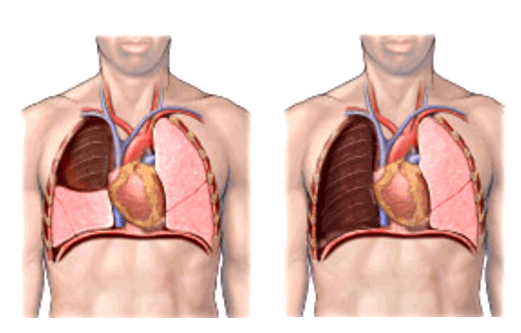

Рисунок 1. КТ брюшной полости ребенка с большой нефробластомой с метастазами в печень.

Клинически: при пальпации опухоль в проекции правой почки до 12 см в диаметре. Общеклинические исследования в пределах возрастной нормы. При КТ органов брюшной и грудной полости: КТ-картина объемного образования правой почки без признаков интрапульмональных метастазов (см. рис. 2). УЗИ брюшной полости: в проекции правой почки солидно-кистозное образование 101ґ114ґ99 мм, объемом 500 мл, васкуляризация активная, интактная часть почки 57ґ12ґ40 мм. Объемное образование правой почки — опухоль Вильмса. Предварительный диагноз: опухоль Вильмса правой почки, 2-я стадия.

Ребенку проведена предоперационная химиотерапия. На 5-й неделе лечения КТ-контроль показал уменьшение опухоли в размерах до 90ґ80ґ100 мм (см. рис. 3).

Выполнена операция: лапаротомия, удаление опухоли правой почки с ее резекцией. Гистологическое заключение: классическая нефробластома, промежуточная группа риска (см. рис. 4).

Рисунок 4. Интраоперационная фотография: резецированная почка (справа), опухолевый узел (слева).